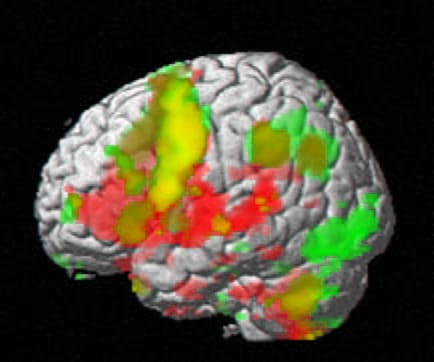

Disponemos de técnicas de imagen que nos indican qué áreas del cerebro están trabajando en cada estado o acción. Podemos aplicar estímulos nocivos y hacer que el cerebro proyecte dolor y registrar la actividad de las áreas responsables.

Al conjunto de áreas activadas cuando el individuo percibe dolor se le conoce como «neuromatrix del dolor».

La puesta en escena de la neuromatrix del dolor ha permitido validar el relato de los pacientes. Si dicen que duele es que duele. La Resonancia magnética funcional evidencia el encendido de la matriz y ese encendido certifica la veracidad del relato. Hay una correlación estrecha entre lo que el paciente cuenta y la matriz ratifica.

Dicen algunos estudiosos que, en realidad, la matriz del dolor no es tal. No es el cerebro del dolor el que se activa sino el de la relevancia («salience»). Duele porque el cerebro atribuye relevancia, trascendencia negativa, nocividad potencial, a un tiempo-espacio somático. En ese momento-lugar y circunstancia al cerebro se le encienden las luces de la probabilidad de daño. Necesita al individuo alerta y colaborador… dolorido.

Podríamos hacer una resonancia magnética funcional y sacar los colores a la neuromatrix de la relevancia. El cerebro atribuye relevancia nociva a un día frío.